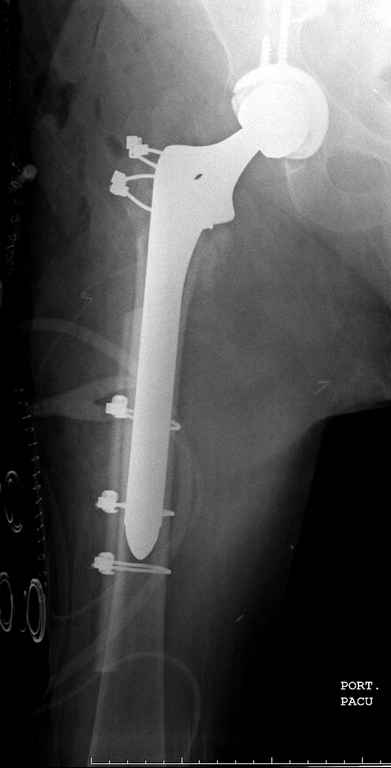

В данном случае в головке бедра и в вертлужной впадине огромный дефект, навряд ли удалением импланта или заменой на другой можно сохранить сустав.

Вашему вниманию представляется похожий случай, пациентке 70, осложнился в течение одного месяца после операции. Ревизия с заменой сустава, кабельная фиксация на трохантер. При установке в дистальном диафизе обнаружен тонкий кортикальный слой и сделана профилактика от возможного перелома аллографтом.

Перечисляя различные техники, хотел бы напомнить, что современный ортопед обязан владеть всеми видами фиксации, включая сложные с обнажением фокуса перелома.